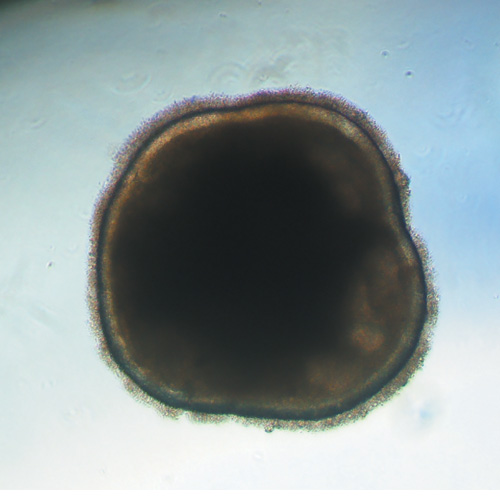

Œil et rétinopathie, du côté de la thérapie cellulaire

Produire des cellules rétiniennes à partir de cellules souches pluripotentes humaines et les greffer dans l’œil pour remplacer les cellules défectueuses : tel est l'objectif de l’équipe d’ Olivier Goureau (Directeur de Recherche INSERM). Forte de ses connaissances sur le développement de la rétine, cette équipe de chercheurs a réussi en partenariat avec l’équipe de la Dr Christelle Monville de I-Stem à créer puis à transplanter un “patch” de cellules de l'épithélium rétinien dérivées de cellules pluripotentes humaines. Cette thérapie génique a dans un premier temps été évaluée sur une lignée de rats porteuse d’une mutation exprimée dans cet épithélium rétinien et causant la perte des photorécepteurs comme il peut être également observé chez certains patients atteints de rétinopathie pigmentaire avec des mutations similaires. Le résultat étant positif sur la survie des photorécepteurs, la non toxicité du patch de cellules a ensuite été évaluée chez des primates non-humains dont le système immunitaire est proche de celui de l’homme. Depuis, un essai clinique de thérapie cellulaire est en cours sur des patients atteints de rétinopathie pigmentaire dont les mutations causales sont exprimées sélectivement dans l’épithélium pigmentaire. Pour cette première clinique, les résultats préliminaires sont très encourageants et les résultats complets devraient prochainement être publiés. Cette thérapie cellulaire testée dans un premier temps sur des patients atteints de rétinopathie pigmentaire pourrait voir son champ d’application s’élargir car certaines pathologies comme la DMLA sont parfois attribuées à un dysfonctionnement des cellules de l’épithélium rétinien.

Organoïde de rétine obtenu à partir de cellules souches humaines © Institut de la Vision